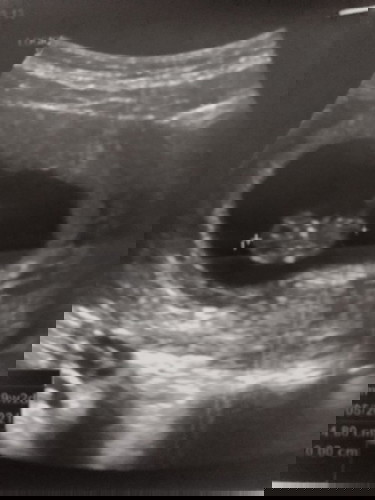

ตอนนี้ตั้งครรภ์ได้10 สัปดาห์ แล้วค่ะมีปัญหาเรื่องการแพ้ท้องมากทานอาหารได้หน่อยเดียว เวลาทานน้ำต้องทานน้ำอุ่น (บ้างทีน้ำร้อนก็มี)ถึงจะทานได้ไม่งั้นอ้วกออกหมด อยากทราบว่าน้ำอุ่นอันตรายกับเด็กในท้องไหมค่ะ แฟนสั่งห้ามให้ทาน ขอคำแนะนำหน่อยคะ🙏😔